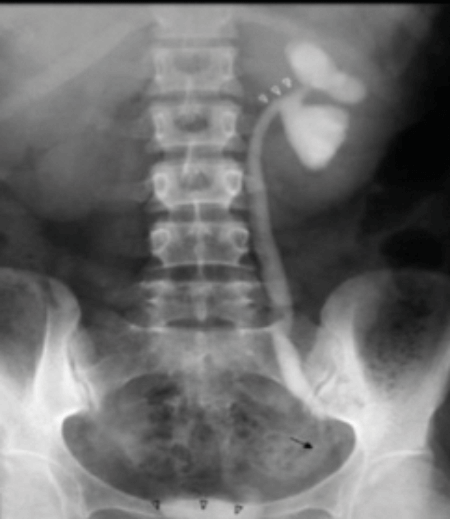

These are a series of radiological images highlighting serious urological infections.

A.

B.

C.

- What are the radiological diagnoses from these images?

- What are the causes of air in the urinary tract?

- Which organisms commonly cause gas in the urinary tract and why?

- Can you define a classification system for emphysematous pyelonephritis?

Case 3

-

a: emphysematous prostatitis

b: emphysematous cystitis

c: emphysematous pyelonephritis.

Recent instrumentation, fistula from genitourinary tract, trauma, infarctions (spontaneous / elective), urinary diversions, infections.

e.coli, candida, klebsiella, proteus. These organisms can cause sugar fermentation and release of carbon dioxide.

Huang-Tseng CT classification:

Class 1: gas in collecting system

Class 2: gas in parenchyma

Class 3a: extension of gas into perinephric space

Class 3b: extension of gas into pararenal space

Class 4: Bilateral or solitary kidney.